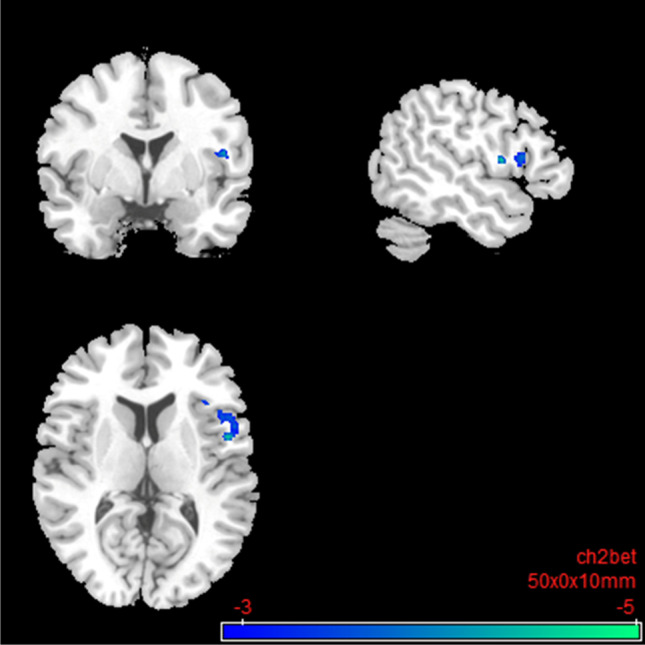

Under nalmefene, the insular cortex showed reduced connectivity to a cluster of frontal (medial frontal and superior frontal gyrus) and paralimbic brain regions (anterior cingulate gyrus and dorsal ACC; Table 4; Fig. 8). Under nalmefene, the ACC showed an elevated rsFC to the right angular gyrus as well as middle temporal gyrus, superior temporal gyrus, inferior temporal gyrus, and parahippocampal gyrus (Table 5; Fig. 9).

Fig. 9.

Salience network: brain regions with increased resting-state functional connectivity between the seed region “anterior cingulate cortex” and the rest of the brain after 18 mg nalmefene compared to placebo (contrast nalmefene > placebo, MNI coordinates: 42 − 56 20). Combined voxel-wise-threshold (p < .01) and cluster-extent threshold k > 372 Voxel, corresponding to pFDR < .05